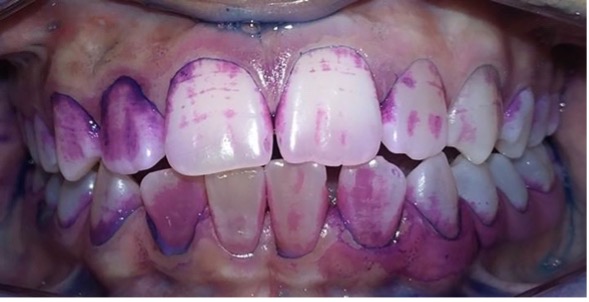

Control de placa bacteriana con revelador doble tono.

Aplicación de barniz de fluoruro de sodio.

Figura 9: Controles integrales periódicos